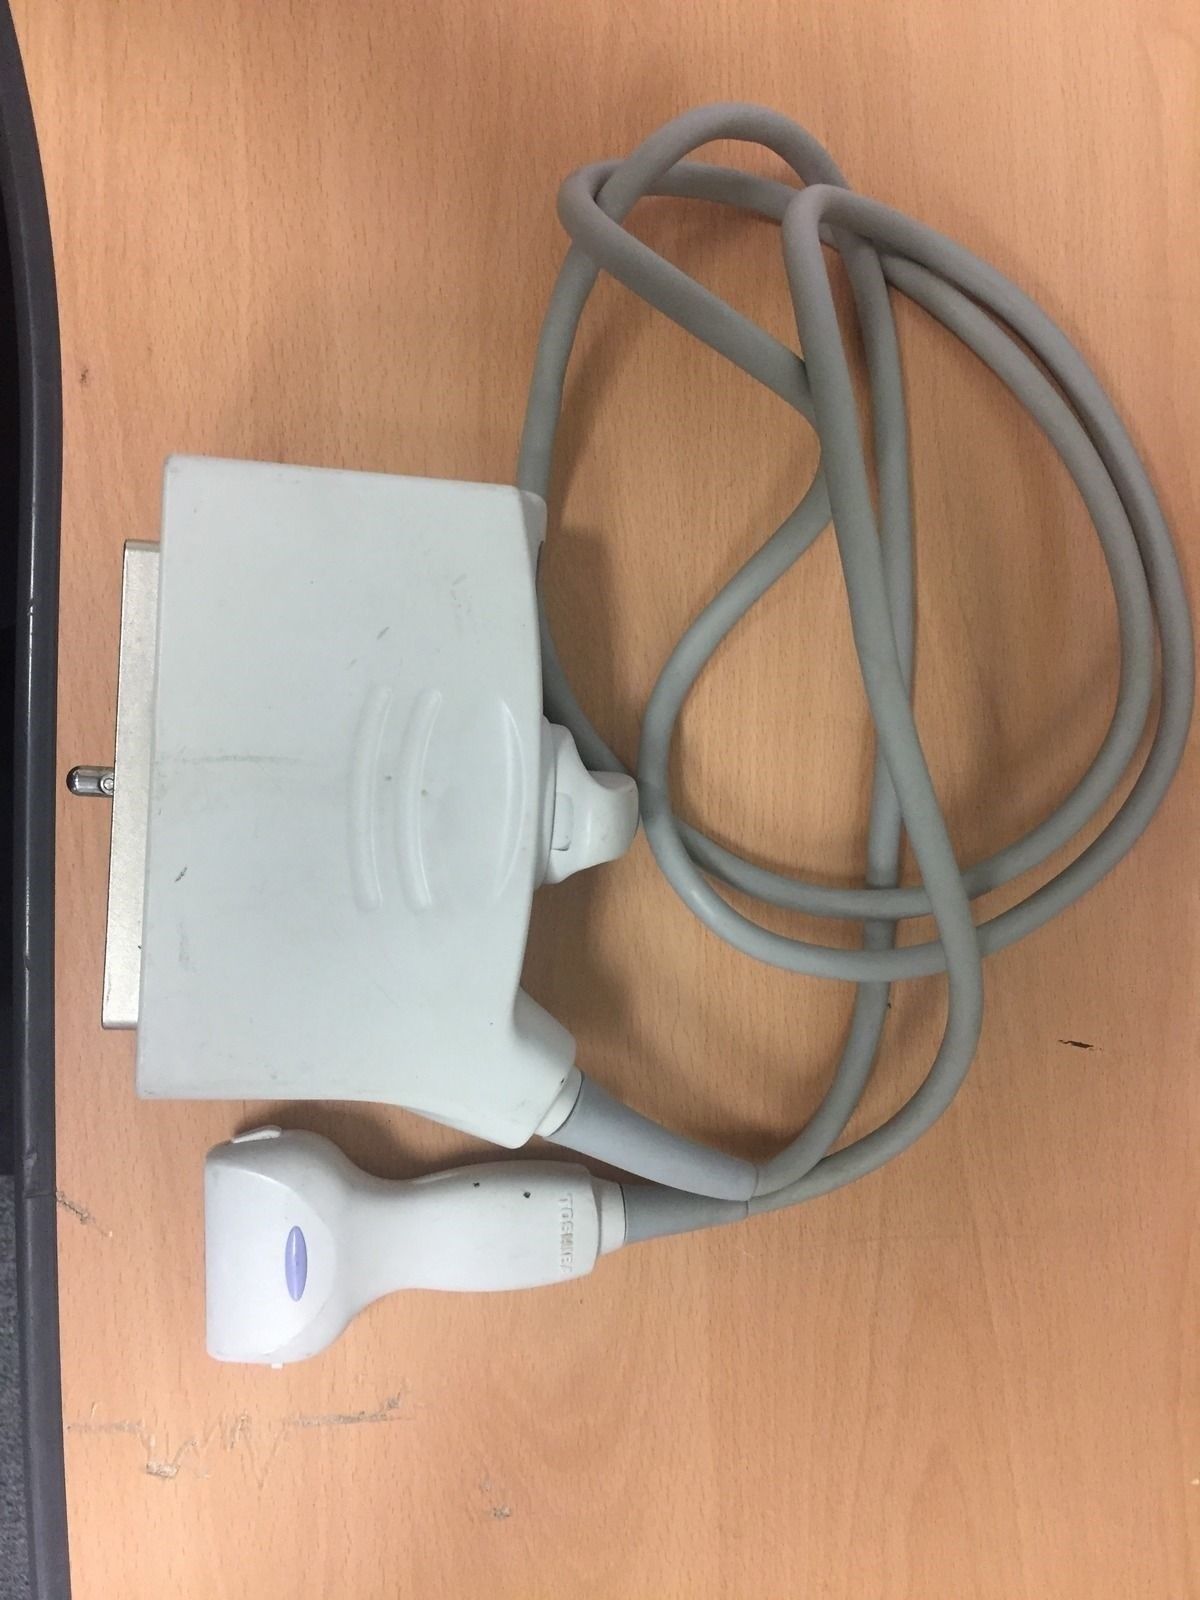

Toshiba Probes

Toshiba Probes

DIAGNOSTIC ULTRASOUND MACHINES FOR SALE